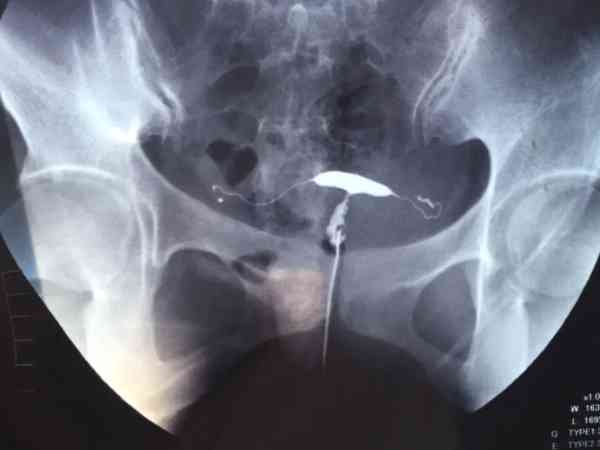

中医不建议没怀过孕的人做输卵管造影,是因为在进行输卵管造影术时,需要使用碘甘油和暴露于辐射,属于不利于怀孕的因素,如果有备孕打算的夫妇,应该在输卵管造影术后三个月左右再考虑备孕,除此之外,输卵管造影会向子宫内注入造影剂,存在有碘过敏等风险,医生会根据病人情况判断是否有必要进行输卵管造影检查。输卵管造影指的是医生使用专业的器械,通过阴道宫腔向输卵管内注入造影剂,可在影像学监测下,通过造影剂在输卵管内...

输卵管造影是要用X线观察造影剂的流动情况,从而判断是否存在堵塞或者其他情况,这种检查输卵管是否存在问题的准确率非常高,基本上已经达到了98%左右,所以检查后发现问题最好及时治疗,如果是常规的输卵管堵塞可能会存在不孕的情况,但若是因为盆腔炎所导致的输卵管堵塞的话,患者还会出现腹痛、分泌物增多等情况,可以自行判断。输卵管造影中文名输卵管造影术适应证不孕症、子宫肿瘤等检查时间月经后3-7天就诊科室妇科检...